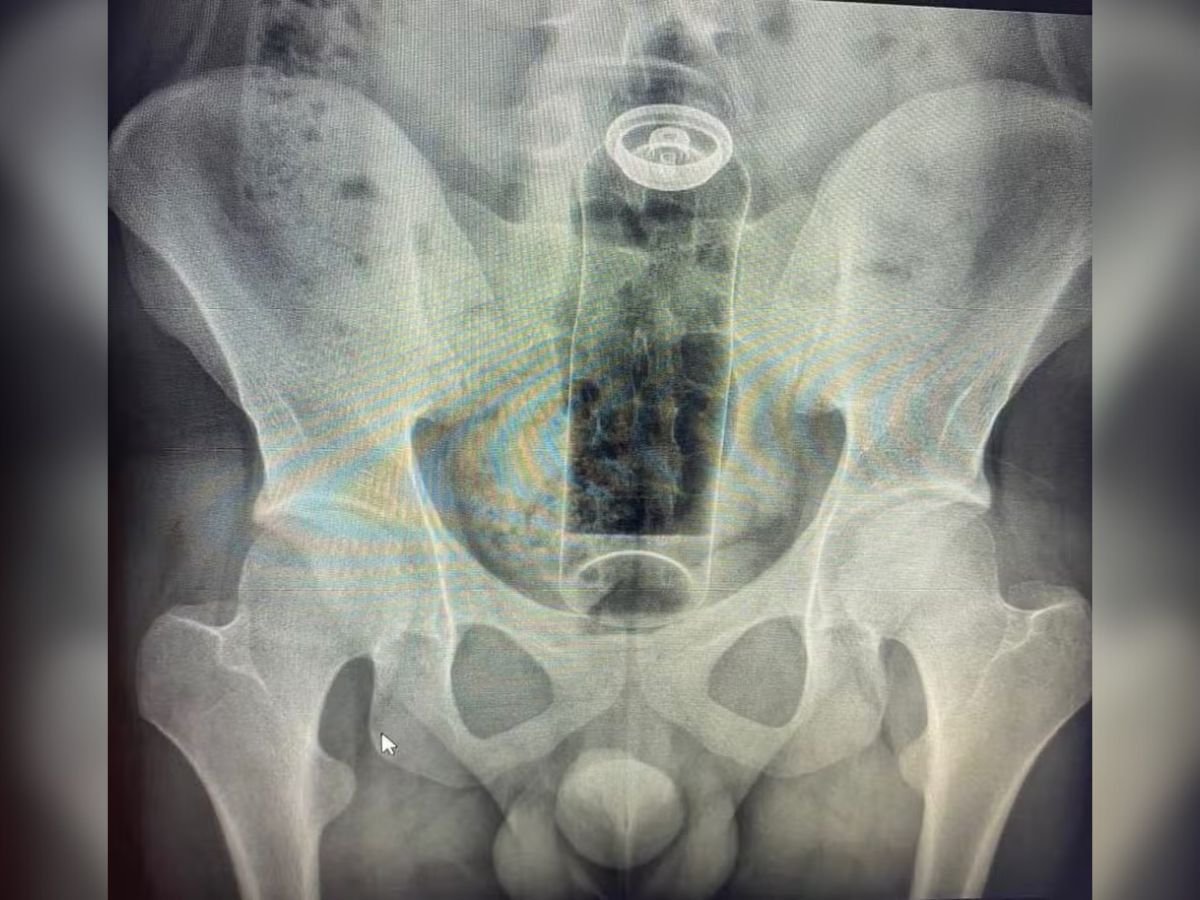

O ex-prefeito do município de Candeias do Jamari (RO) Valteir Queiroz foi preso por porte ilegal de arma de fogo na noite desta sexta-feira (16) no posto de fiscalização da Polícia Rodoviária Federal, na BR-364, em Porto Velho.

Segundo informações repassadas pela polícia rodoviária federal, durante uma fiscalização que estava sendo realizada, o político foi flagrado com um revólver dentro do carro em que estava dirigindo.

Ao ser questionado pela polícia sobre o certificado de registro de arma de fogo, Valteir informou não possuir documentos necessários, mediante a isso, os policiais deram voz de prisão e o conduziu para o Departamento de Flagrantes na capital rondoniense.